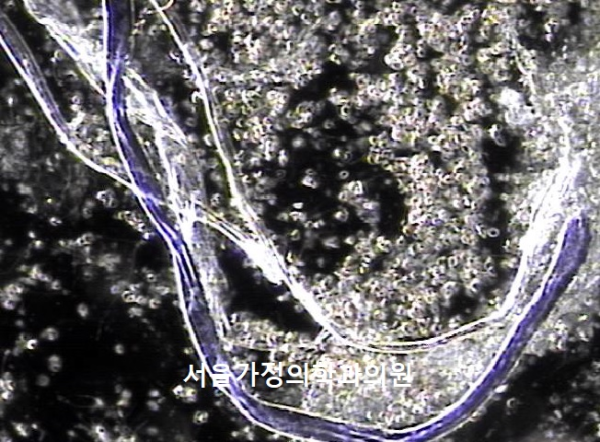

주 1회 치료중 정낭에서 생산되는 염증 즉 프로스타그란딘 R로 생긴 염증 덩어리와 탈락된 거짓 중층 원주 상피세포의 치료된 현미경 학적 자료입니다.

This microscopic image shows the treated tissue from the seminal vesicles. It includes inflammatory clumps caused by prostaglandin-related inflammation, along with shed epithelial cells that had been blocking the ducts. These findings show that the treatment is helping to clear away these causes and improve circulation.

This microscopic image shows the resolution of inflammatory clusters, caused by prostaglandin R produced in the seminal vesicles, along with shed pseudostratified columnar epithelial cells, following once- or twice-weekly treatment.